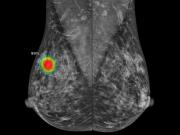

La investigación liderada por Google y el NHS marcó un punto de inflexión en la lucha contra el cáncer de mama. El sistema experimental analizó las mamografías de 115.973 mujeres y detectó una mayor cantidad de casos invasivos que los métodos convencionales.La tasa de... + más